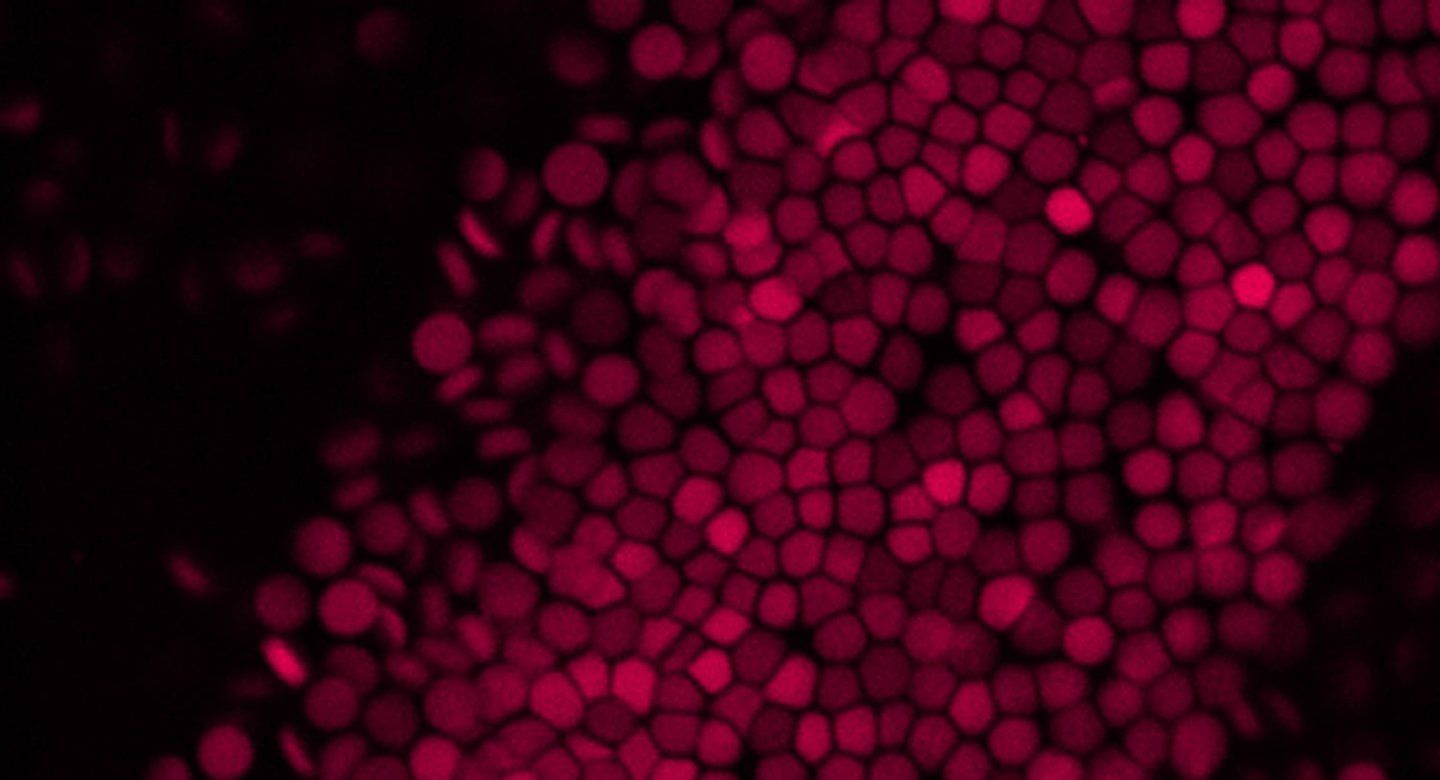

Structural Surfaceomics Reveals an AML Specific Conformation of Integrin-β2 as an Immunotherapeutic Target

First author Kamal Mandal, PhD, discusses how the research team explored the hypothesis that tumor surface antigens may harbor cancer-specific protein conformations, invisible to standard target discovery strategies focusing on gene or protein expression alone, that may create selective immunotherapy targets. Their results underscore the potential of “structural surfaceomics” to expand the toolkit of target discovery in cancer, with possible applications in other diseases, while motivating further preclinical evaluation of aITGB2 CAR-Ts in acute myeloid leukemia (AML). Mandal is a UCSF postdoctoral scholar working in the Arun Wiita Lab. Arun Wiita, MD, PhD, is senior author of the study and an associate professor of laboratory medicine at UCSF.

Abstract 357